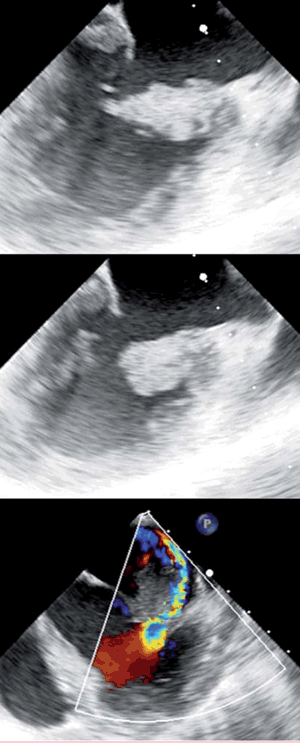

Se planteó una EI indicándose ecocardiograma transtorácico (ETT) que mostró una vegetación en el velo anterior de la válvula mitral, de 20 por 21 mm, friable; insuficiencia mitral (IM) severa; aurícula izquierda (AI) dilatada; ventrículo izquierdo de dimensiones y función normales (figura 1).

Arriba y centro: vista ecocardiográfica (ETE) de la vegetación mitral, implantada fundamentalmente en la valva anterior. Abajo: regurgitación mitral excéntrica severa, con efecto coanda que alcanza el techo de la aurícula izquierda.

En el ETT se encontró una vegetación (criterio diagnóstico mayor) gigante y friable de la valva anterior mitral. Estas características están relacionadas con el mayor riesgo embólico. El trombo determinaba, además, IM severa (libre) por déficit de coaptación valvar. La AI se encontraba dilatada, lo que es sugestivo de enfermedad mitral previa. Se realizó ETE que no encontró otras lesiones anatómicas.